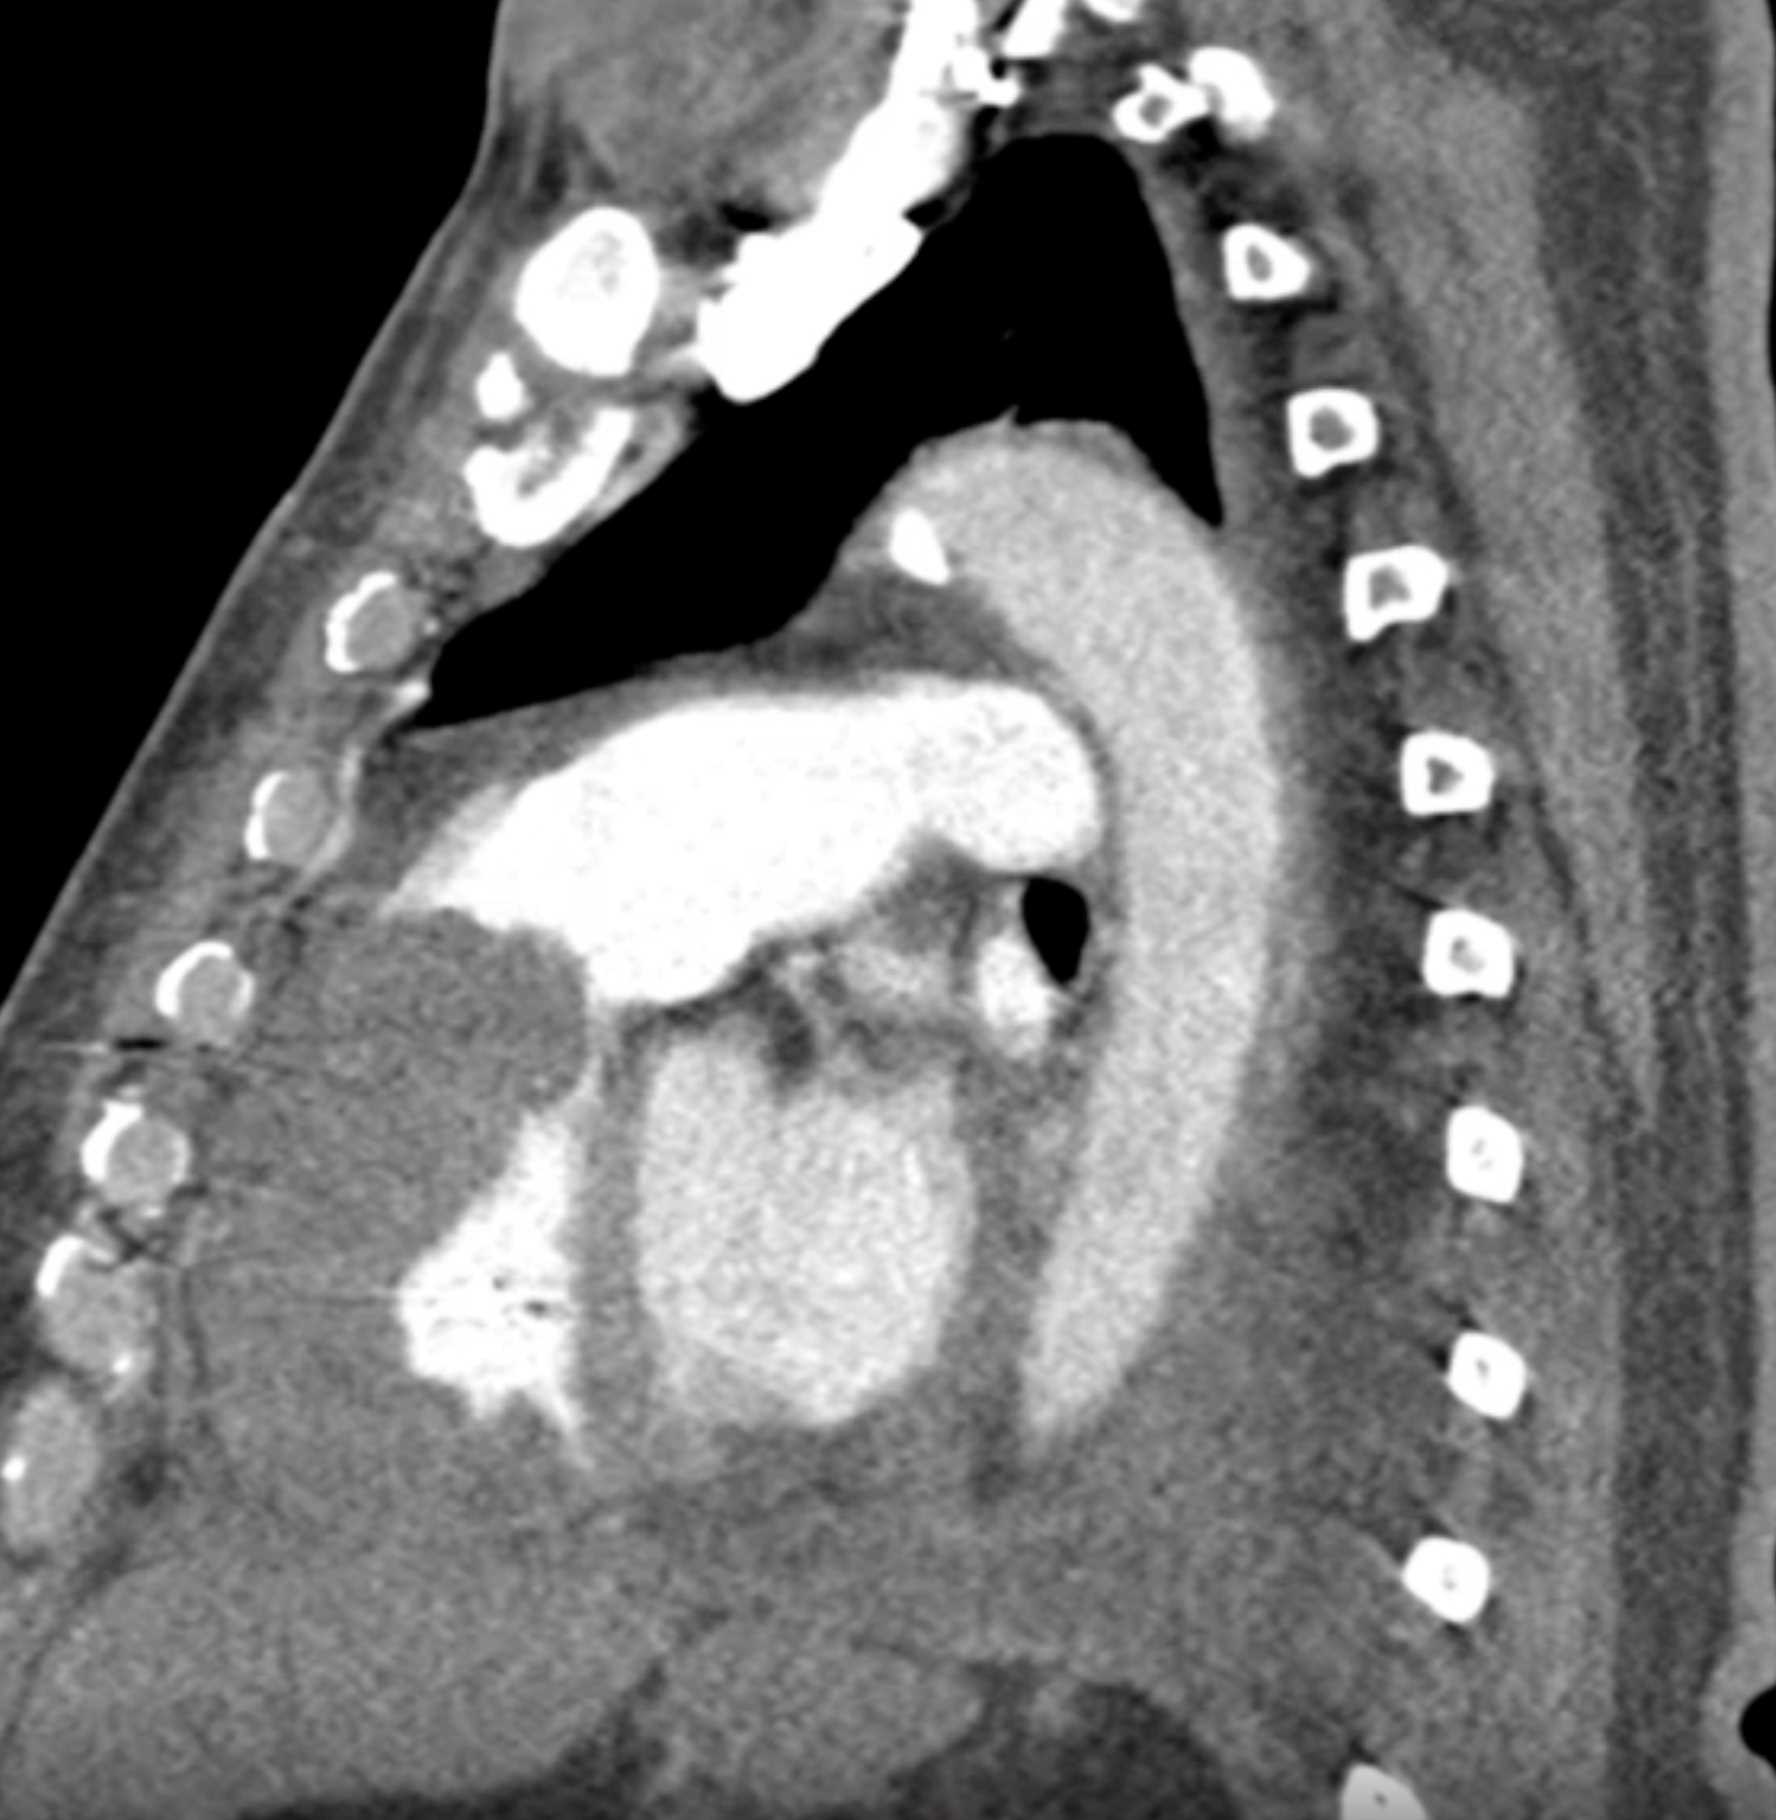

Primary Spindle Cell Carcinoma of the Right Ventricle